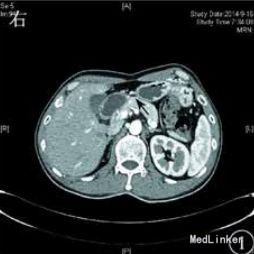

体查:振水音阳性,行胃肠减压引流胃液及胆汁>1000 mL/d。腹部立位X线片未见异常。复查增强 CT和腹部血管造影示:十二指肠水平部狭窄伴前方肠系膜血管压迫,考虑肠系膜血管压迫综合征。

予加强静脉营养、内科保守治疗,无好转,再行上消化道碘油造影示十二指肠水平部狭窄,造影剂无法通过,采取俯卧位后造影剂可通过,但十二指肠升部与空肠交界处狭窄,造影剂无法通过。考虑存在十二指肠与空肠交界处病变,恶性肿瘤不能排除,遂决定手术探查。术中在十二指肠升部与空肠交界处可见一肿瘤,最大径约为3cm,累及浆膜,相应肠管狭窄梗阻,系膜可见肿大淋巴结,另可见肠系膜上血管与腹主动脉间脂肪组织减少,十二指肠水平部部分被压迫,探查其余小肠及结肠未见异常,肝脏、盆腔、腹主动脉旁未见明显转移,腹腔未见腹水。术后病理诊断示小肠中至低分化腺癌,侵及浆膜外脂肪组织,脉管中见癌栓。上、下切端均未见癌组织累及,周围脂肪组织中的16枚淋巴结中5枚见转移性癌组织,另见癌结节2枚。免疫组织化学检查示,细胞角蛋白7阴性,细胞角蛋白20、CEA 、绒毛蛋白、细胞角蛋白19、CA19-9和 CD34血管阳性,Ki‐67抗原约85%阳性。术后患者恢复良好,无恶心、呕吐,出院后胃纳正常。1个月后复诊体质量增加约5 kg。